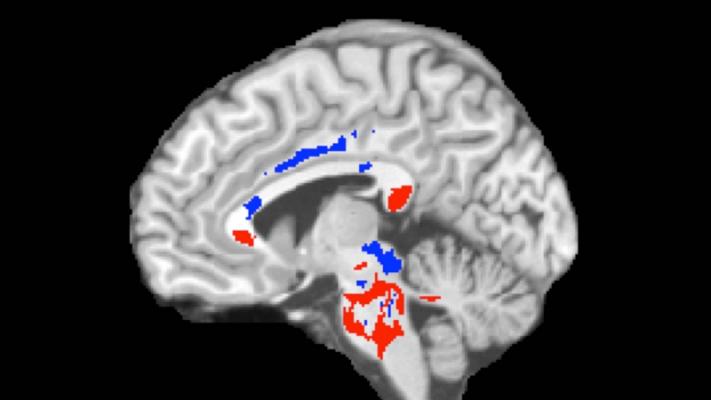

This image of a concussion patient's brain shows low FA areas (red) probably signifying injured white matter, plus high FA areas (blue) perhaps indicating more efficient white-matter connections compensating for concussion damage. A large amount of high FA predicts recovery from concussion. Image courtesy of PRNewsFoto/Albert Einstein College of Med.

DTI imaging comparing concussion patients and healthy controls revealed two types of white-matter abnormalities in patients: (1) areas of abnormally low FA (red, in associated image) that correlate with axon damage and the cognitive impairment that can affect concussion patients; and (2) other brain areas with abnormally high FA (blue) that may indicate where the brain has responded favorably to injury, perhaps by more efficiently connecting axons or by remyelinating injured tissue (i.e., forming fatty tissue around nerves, which allows nerve impulses to move more quickly).

The amount of high FA imaged in brains predicted patients' outcomes following concussion. Having a greater volume of abnormally high FA white-matter areas (perhaps indicating good compensation for concussion damage) was associated with better outcomes on follow-up assessments. (This doesn't mean that the low FA areas showing white-matter damage aren't important — just that they're not useful in predicting recovery from concussion a year later.)